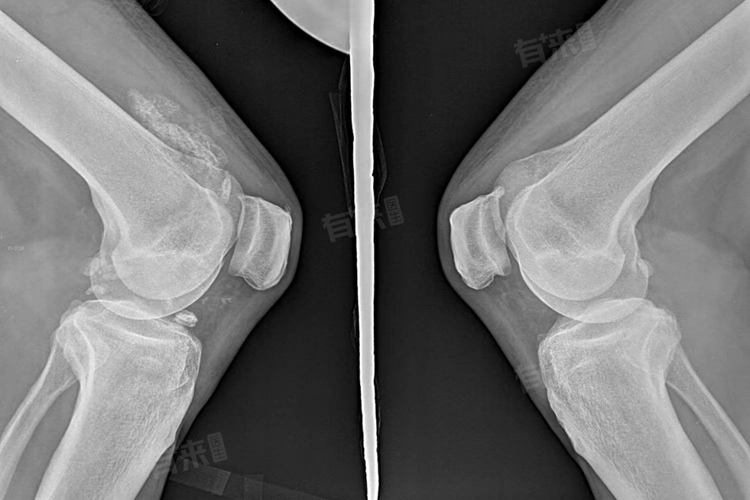

检查疾病的方法主要包括体格检查,医生会仔细观察患者的膝盖形态、活动度以及是否存在压痛等症状,以及影像学检查,如X线、MRI等影像学检查方法可以帮助医生更准确地了解关节内部结构、软骨磨损情况以及是否存在其他异常。